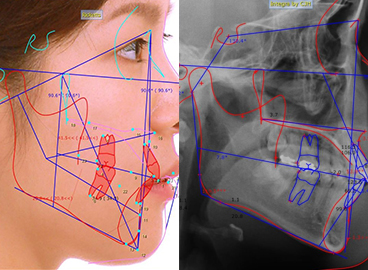

3D precision analysis — detailed treatment planning

Digital 3D analysis enables accurate, highly detailed planning for refined orthodontic outcomes.

• AI-powered orthodontic simulation

A precision analysis program based on a globally recognized diagnostic system for pre-treatment diagnosis, growth analysis, prediction, and orthognathic assessment.

• Preview Results

View a time-lapse simulation of before & after changes.

• Wide Clinical Range

Applicable across a wide range of clinical cases.

• Detailed Planning

Multiple analysis methods for more precise treatment planning.